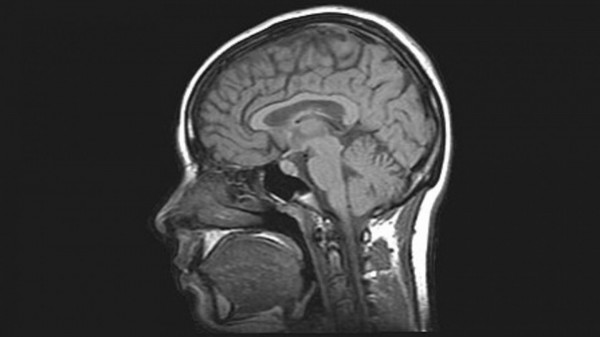

Εγκεφαλικό επεισόδιο και ενδοκρανιακή αιμορραγία οι συχνότερες επιπλοκές.